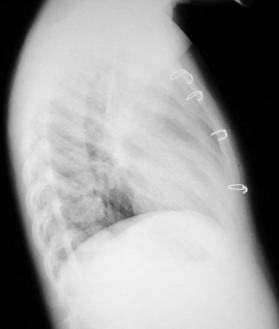

Radiografía del tórax

Rx. Tórax PA. Radio transparencia conservada en ambos campos pulmonares, sin infiltrados parenquimatosos, hileo y patrón de flujo pulmonar normal, senos costo y cardio-diafragmaticos libres, silueta cardiaca posición central normal, puede notarse el ensanchamiento del mediastino, por loe mas prominente en el lado derecho aspecto lobulado bien limitado, el esqueleto y partes blandas sin alteraciones.

Rx. Tórax LI. Radiopacidad peritraqueal redondeada y lobulada prominente en mediastino anterior y superior que incrementa el contraste de radiotrasperencia traqueal, observándose estenosis en su porción distal.